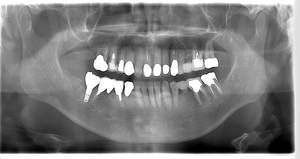

インプラント治療の症例3

レントゲン写真

- Befor

- After

| 年齢 | 50代・男性 |

|---|---|

| 主訴 | 左下7番 |

| 治療内容 | 右下7番インプラント埋入 |

| 治療費 | 合計:572,000円 診断料:55,000円 埋入料:165,000円 サージカルガイド:55,000円 静脈内鎮静麻酔:77,000円 仮歯:55,000円 上部構造(フルジルコニア):165,000円 (2023年1月現在) |

| 治療期間 | 約8ヶ月 |

| 治療方針 | 骨が十分にあるため、骨造成をすることなく埋入した。かみ合わせが強いので、負荷がかからないよう、夜寝るときにマウスピースをつけるよう指示をした。 |

| 担当者所見 | 左下6番7番のインプラントは他院で埋入しており、右下7番は抜歯したままで、かみ合わせの歯が落ちてきてしまうのでインプラントを埋入しました。 |